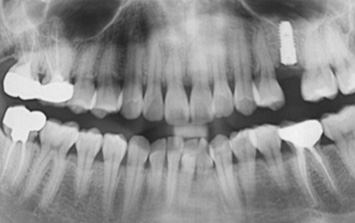

오른쪽 앞니 상실로 내원한 환자분. 앞니의 상실로 치아 사이 틈이 넓어지고 있어 교정으로 임플란트 식립 공간을 만든 후

임플란트 식립을 하였습니다. 앞니가 상실된 기간이 길어 교정치료를 하지 않고 임플란트를 식립할 경우

벌어진 치아 사이로 음식물이 끼거나 치아형태 이상으로 문제가 생길 수 있습니다.